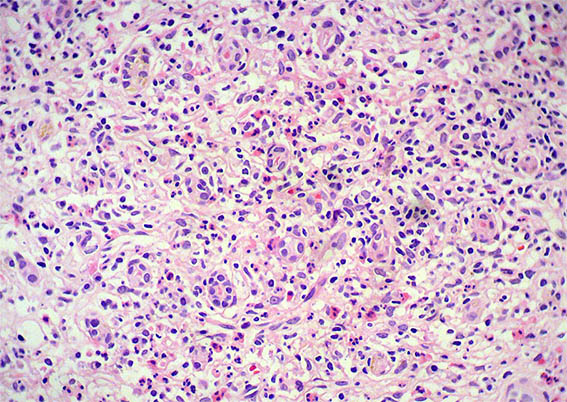

Figura 2. H&E, X200.